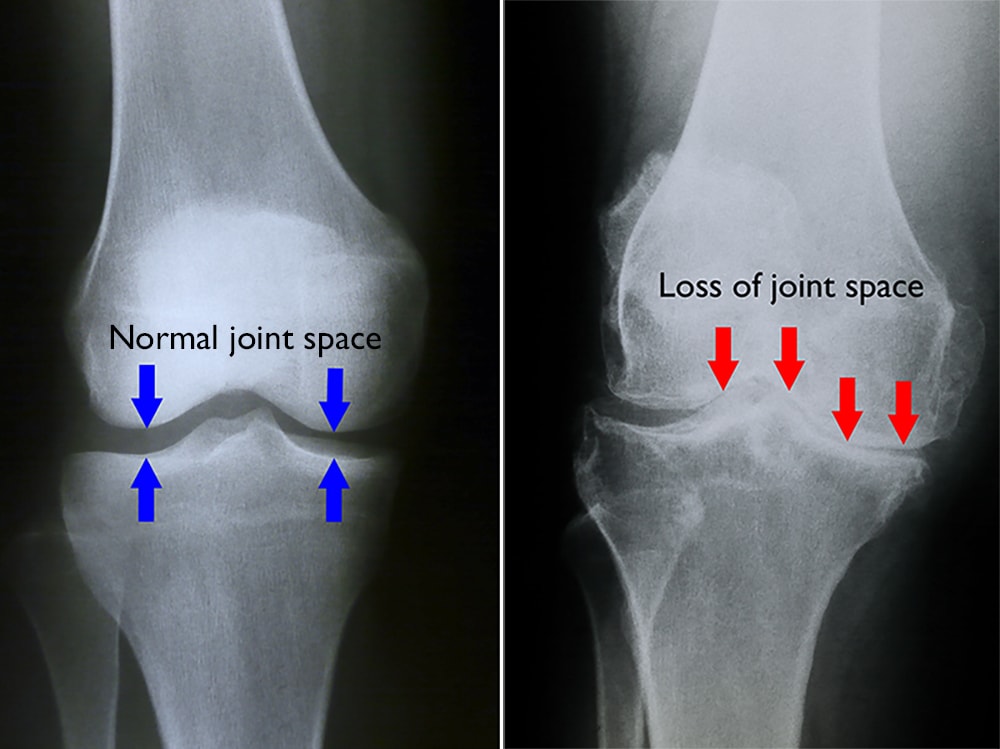

X-rays. X-rays provide images of dense structures, such as bone. Although a cyst cannot be seen on an X-ray, your doctor may order one to look for narrowing of the joint space and other signs of arthritis in the joint.

normal and arthritic knee

(Left) In this X-ray of a normal knee, the space between the bones indicates healthy cartilage. (Right) This X-ray of an arthritic knee shows severe loss of joint space.